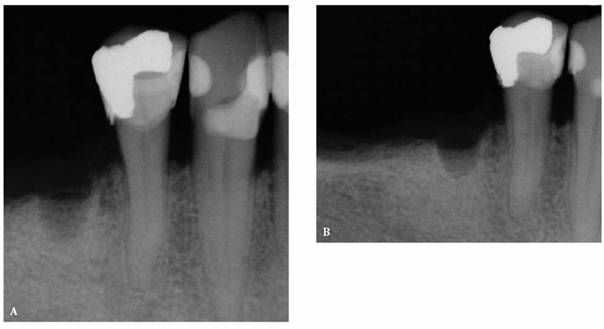

In most cases, an endodontic procedure should not be initiated without

evaluating at least two recent radiographs exposed at different horizontal

angulations of the suspected tooth (Figures 19-24A

and B).

Comparing varied views is essential in diagnosing the presence of additional

roots, anatomic configurations, anomalies, and other unusual circumstances that

may complicate the treatment.

Figure 19-24A and B: (A) Pretreatment radiograph of a mandibular premolar shows one canal. (B) A second radiograph taken from an angulation of 15 degrees from the mesial discloses a second root.